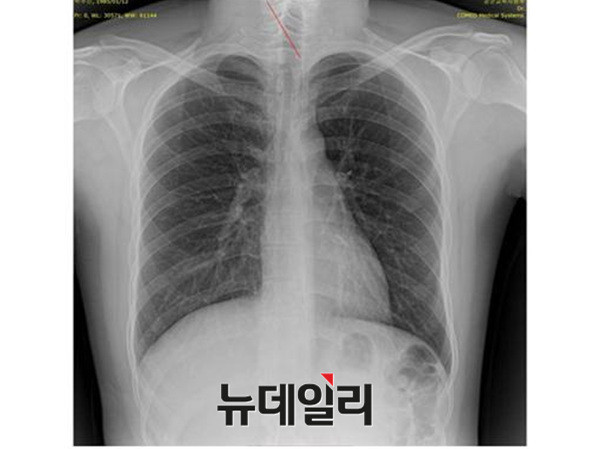

- ▲ 박주신씨 명의의 자생병원 엑스레이. ⓒ 뉴데일리DB

반면 지난해 12월부터 시작된 양승오 박사 등 시민 7명에 대한 공직선거법 위한 공판을 통해 새롭게 밝혀진, 박주신씨의 ‘공군훈련소 입소 당시 엑스레이’(촬영일자 2011년 8월 30일, 이하 공군 엑스레이)와, 주신씨가 ‘비자발급을 위해 촬영한 세브란스병원 엑스레이’(촬영일자 2014년 7월 31일, 이하 비자발급용 엑스레이)는 각각 박주신씨 본인의 신체를 촬영한 것으로 받아들여지고 있다.

- ▲ 박주신씨 공군훈련소 입소 당시 촬영된 엑스레이. ⓒ 뉴데일리DB

- ▲ 박주신씨가 지난해 7월 비자발급을 위해 촬영한 엑스레이. ⓒ 뉴데일리DB

이들 세 개의 엑스레이는 모두 박주신씨의 신체를 촬영한 것으로 알려져 있기 때문에, 이들 엑스레이에 대한 판독결과 피사체를 동일인으로 볼 수 없는 유의미한 차이점이 발견된다면, 이는 박주신씨의 대리신검 혹은 영상자료 바꿔치기 의혹을 뒷받침하는 결정적 단서가 된다.

세계적 권위를 인정받은 영상의학 전문의인 양승오 박사(동남권원자력의학원 암센터 핵의학과 주임과장)와 치과의사 김우현씨 등 박주신씨 병역비리 의혹을 주장해 온 시민들은, 위에서 언급한 세 개의 엑스레이에 대한 비교 판독 결과, 이들 엑스레이를 같은 사람의 것으로 볼 수 없는 차이점을 발견하고 이를 재판부에 증거자료로 제출했다.

- ▲ ▲박주신의 자생병원 X-Ray(왼쪽)과 공군 X-Ray(오른쪽). 자생병원의 엑스레이에서는 오른쪽 제1늑골부위에 '석회화'현상이 보이지만 공군엑스레이에선 보이지 않는다. ⓒ 뉴데일리DB

박주신씨의 자생병원 X-Ray를 보면, 오른쪽 제1 늑골부위에 ‘석회화’ 현상이 나타난다. 그러나 주신씨가 공군 입대 당시 찍은 X-Ray에는 이런 모습이 전혀 보이지 않는다.

이런 차이에 대해 양승오 박사의 변호인인 차기환 변호사 등은 "각각의 X-Ray를 찍은 사람이 동일인이 아니라는 것을 입증한다"고 설명했다.

‘극상돌기’의 경우에도 차이점은 명확히 드러난다.

변호인 측은 “공군에서 찍은 엑스레이와 비자발급을 위해 찍은 엑스레이에서는 피사체의 제 1흉추 극상돌기가 오른쪽으로 휘어있지만, 자생병원에서 찍은 영상에서는 정방향으로 나온다”며, “박주신씨가 공군에 입대해 찍은 엑스레이와 세브란스 공개신검에서 나타난 피사체의 의학적 차이가 명확해 동일인이라고 인정할 수 없다”고 지적했다.

우리가 흔히 등을 만지면, 가운데 뾰족하게 솟아난 부분이 바로 ‘극상돌기’다.

흉추를 비롯해 모든 척추에 존재하며, 흉추에 외상이나 수술, 질병 등이 없었던 근접한 기간 동안 촬영된 엑스레이에서 극상돌기의 형태가 명확하게 다를 경우, 다른 개체라고 판단할 의학적 근거가 된다.